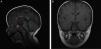

Case 2The patient was a newborn boy born after a full-term pregnancy with a history of symptomatic hypoglycaemia at birth, mucocutaneous jaundice treated with phototherapy, weak suck, and pronounced cervicoaxial hypotonia; the neonatal examination yielded normal results. At the age of 12 months, a laboratory test performed due to persistence of hypotonia, inability to sit up, and persistent constipation revealed free T4 levels of 0.50ng/dL and TSH levels of 2.34μIU/mL. All other findings for the hypothalamic-pituitary axis were normal (glycaemia, ACTH, cortisol, LH, FSH, testosterone, prolactin, IGF-1, and IGFBP-3). We started treatment with oral levothyroxine (25μg/day) for central hypothyroidism, which improved the constipation and psychomotor development. The patient presented hypoplastic scrotum, retractile testes, and penis length in the lower threshold of normality. At the age of 2, he presented significant asthenia after playing and somnolence accompanied by clumsiness and frequent falls; cortisol levels were 2.71μg/dL (normal range, 5-25); ACTH (7.7pg/mL, normal range, 5-46) and ion values were normal. We started hormone replacement therapy with hydrocortisone, which improved the symptoms. The MRI scan showed moderate anterior pituitary hypoplasia, ectopic posterior pituitary at the median eminence, and complete agenesis of the pituitary stalk (Fig. 1A and B). A genetic test yielded normal results.

Diagnosis is established based on clinical findings and hormone level measurements (initially alterations in GH levels and the thyroid axis [TSH], followed by alterations to the adrenal [ACTH] or gonadal axis [LH/FSH], and lastly, altered prolactin levels). Diagnosis is confirmed by molecular studies or MRI, which reveals a variable lesion spectrum (small sella turcica, hypoplastic or aplastic pituitary, lack of pituitary stalk, and lack of hyperintensity in the posterior pituitary area). Treatment for hypopituitarism consists in treating the hormone deficiencies.6